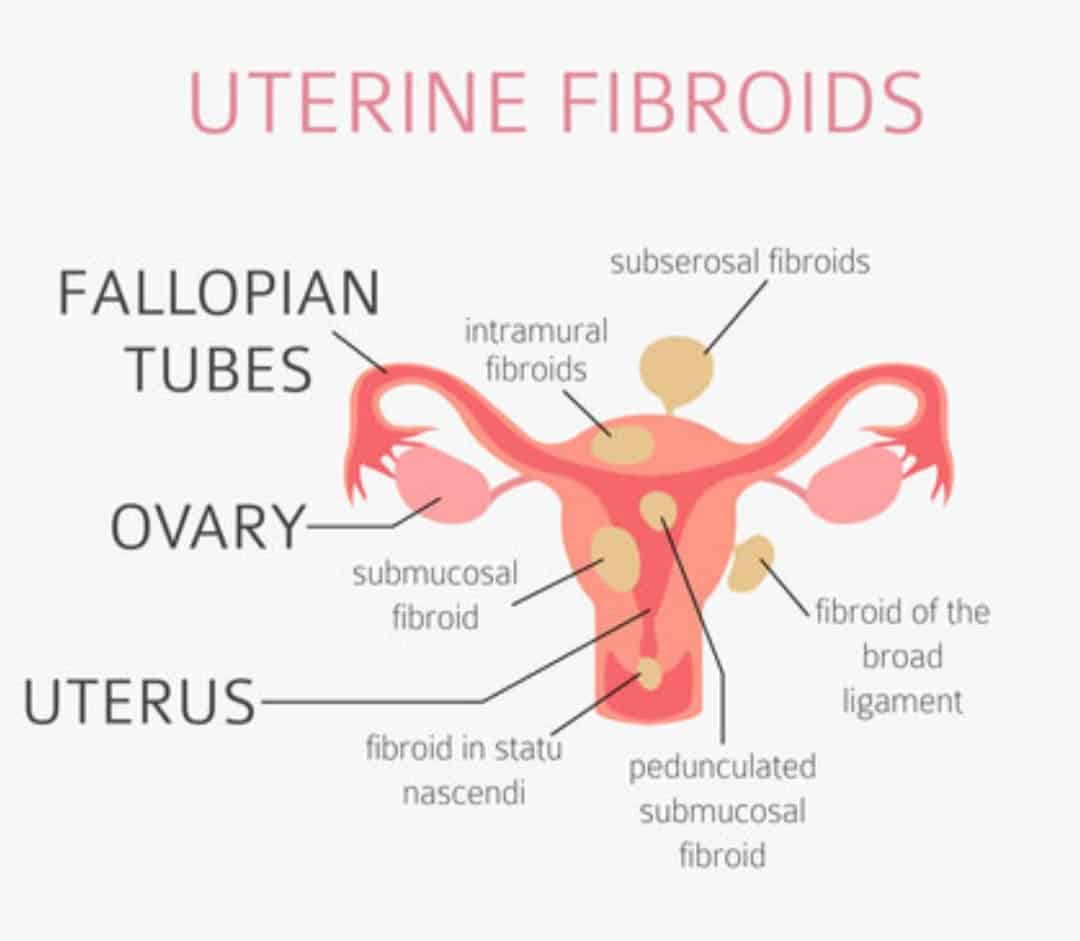

What Are Fibroids? – Angea

Types of Uterine Fibroids – Dr Pamela Tan | Uterine fibroids, Fibroids …

Types of Fibroid’s? | Fibroids, Hospital, Intramural

Uterine fibroids. Fibroid types and uterine fibroids treatment | MED Expert